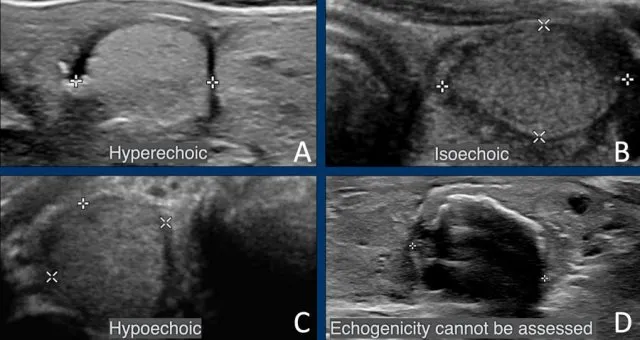

Thyroid USG: Risk stratifies nodules. High-risk features: microcalcifications, marked hypoechogenicity, irregular margins, taller-than-wide, extrathyroidal extension, suspicious nodes. ACR TI-RADS (TR1-TR5) score guides FNAC.